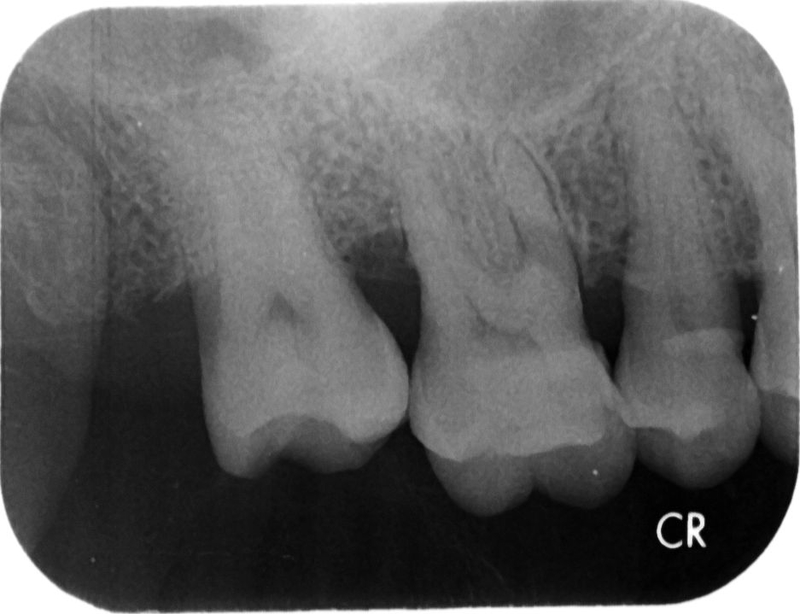

- 裂齒或斷齒:在進食或睡眠中舌環不小心撞到牙齒,造成牙齒的損傷,輕則須修復牙齒,重則牙齒需拔掉。

- 不良習慣:舌環畢竟是外來異物,有時會不自覺養成舌頭不自主運動,如吐舌或是推擠門牙造成牙齒位移,開縫(Spacing)或是開咬(Open Bite)。